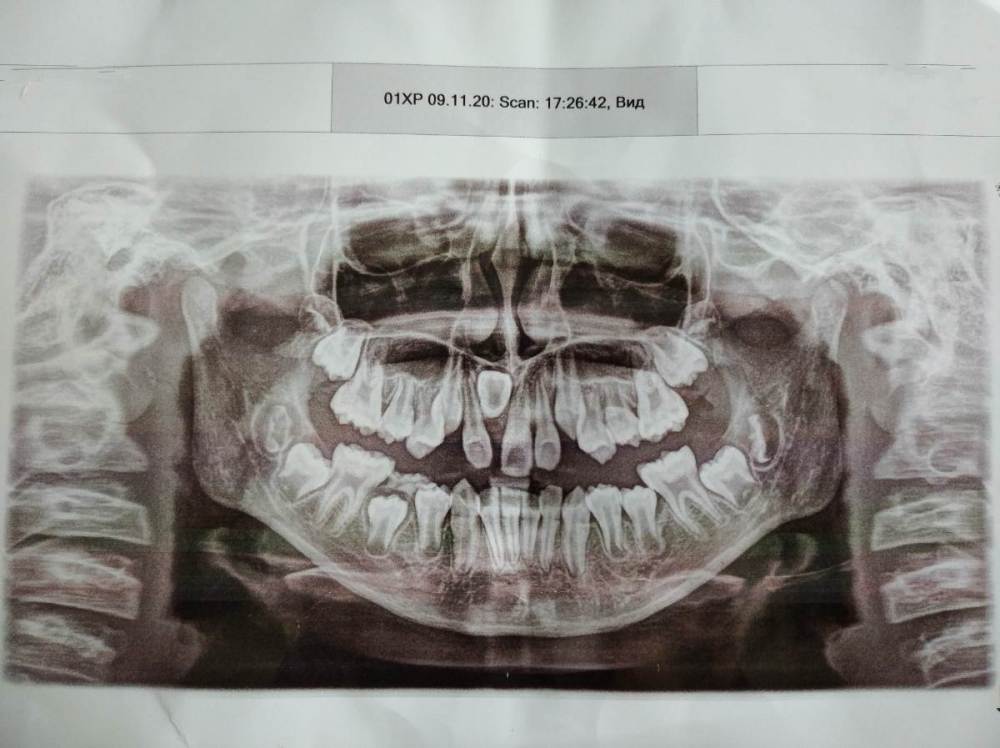

Kri_ssty Опубликовано 12 июня, 2021 Поделиться Опубликовано 12 июня, 2021 (изменено) Посоветуйте, пожалуйста, что можно сделать в этом случае? Ребенку 11 лет. Изменено 12 июня, 2021 пользователем Kri_ssty Ссылка на комментарий